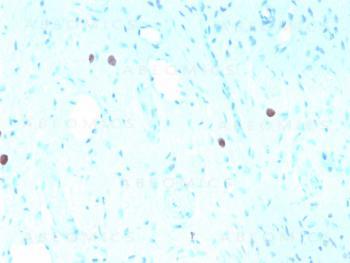

Fig. 1: Formalin-fixed, paraffin-embedded human Cervix stained with HPV-16 Mouse Recombinant Monoclonal Antibody (rHPV16L1/1058).

Immunohistology (Formalin-paraffin) (1-2ug/ml for 30 minutes at RT),(Staining of formalin-fixed tissues requires boiling tissue sections in 10mM citrate buffer, pH 6.0, for 10-20 min followed by cooling at RT for 20 minutes),